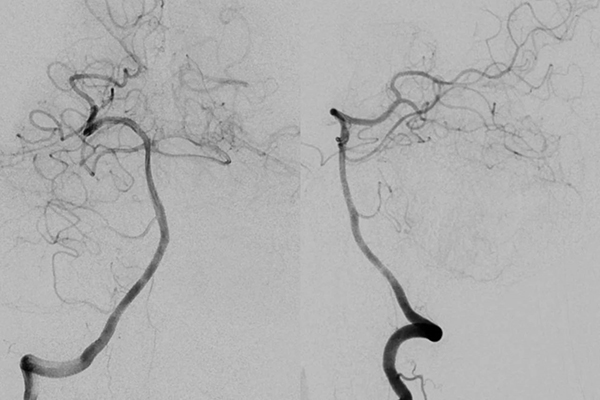

▲右侧椎动脉正侧位造影未见明显异常